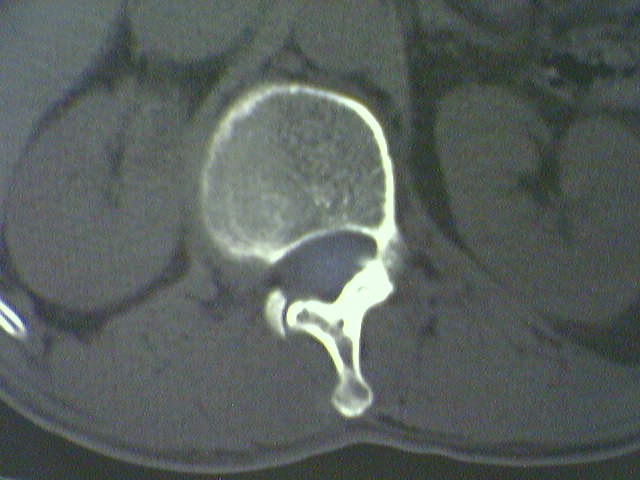

标题: CT15569:男,45岁.腰痛多年,平片腰椎明显侧弯, [打印本页]

标题: CT15569:男,45岁.腰痛多年,平片腰椎明显侧弯,

退行性骨增生软组织硬化;应有平片以除外椎体滑脱

支持侧弯致退行性骨关节病。

支持腰椎侧弯致退行性骨关节病。